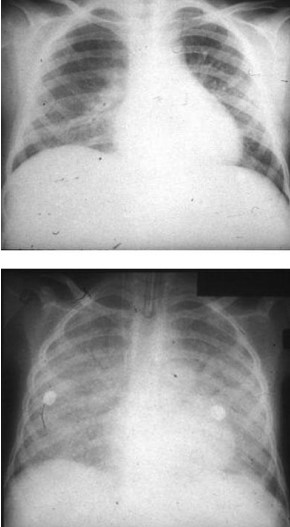

Common X-ray Findings: